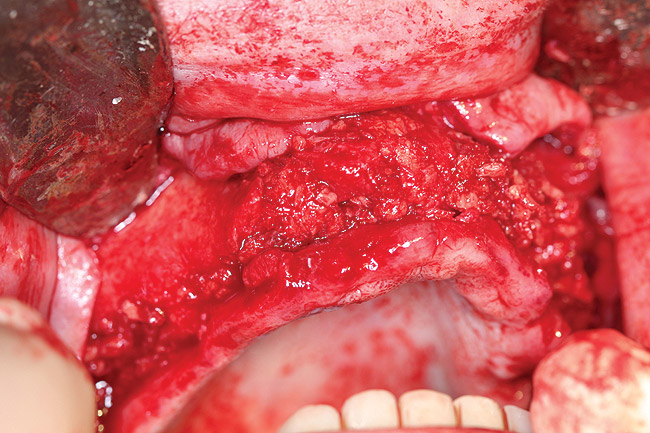

A DFDBA bone-graft putty (Regeneform) was used to graft the entire maxillary arch. All extraction defects were degranulated, the bone was decorticated to allow bleeding, then the DFDBA putty was placed and covered with resorbable collagen membranes (Biomend Extend, Zimmer Dental) (Figure 5). Primary closure was obtained and the patient wore her denture after a soft reline for a period of 6 months (Figure 6). At 6 months post-graft, a CBCT scan revealed substantial graft material from both an axial (Figure 7) and a crosssectional view, showing more than 15 mm of bone height (Figure 8). The 3D view from the CBCT also showed substantial ridge changes in both height and width (Figure 9). Using a CBCT software program (SimPlant, Materialise Dental Inc, Glen Burnie, MD), implants were planned for placement (Figure 10). As per the CBCT plan, 11 internal hex implants (BioHorizons, Birmingham, AL) were placed in the grafted bone (Figure 11). The ideal bone height allowed implant placement in an ideal position with relation to esthetics and occlusion.

Figure 11  Clinical view of internal hex implant placement in grafted bone.

Figure 11

After 6 months of healing, a CBCT scan was taken and good bone formation was seen on the axial (Figure 18) and panograph (Figure 19) views. The CBCT was then used to plan for placement of dental implants (Figure 20). Upon full-thickness reflection of the ridge, abundant bone contour was observed. Internal hex dental implants (BioHorizons) were placed according to the locations planned on the CBCT (Figure 21). After a healing period of 4 months, the implants were uncovered (Figure 22) and abutments were placed (Figure 23). A panograph taken 1 year after this stage revealed the final restorations on well-integrated implants (Figure 24). The patient’s smile reveals a fixed prosthesis that simulates her natural teeth (Figure 25).

Figure 21  Clinical view of implant placement 6 months post-graft healing.

Figure 21